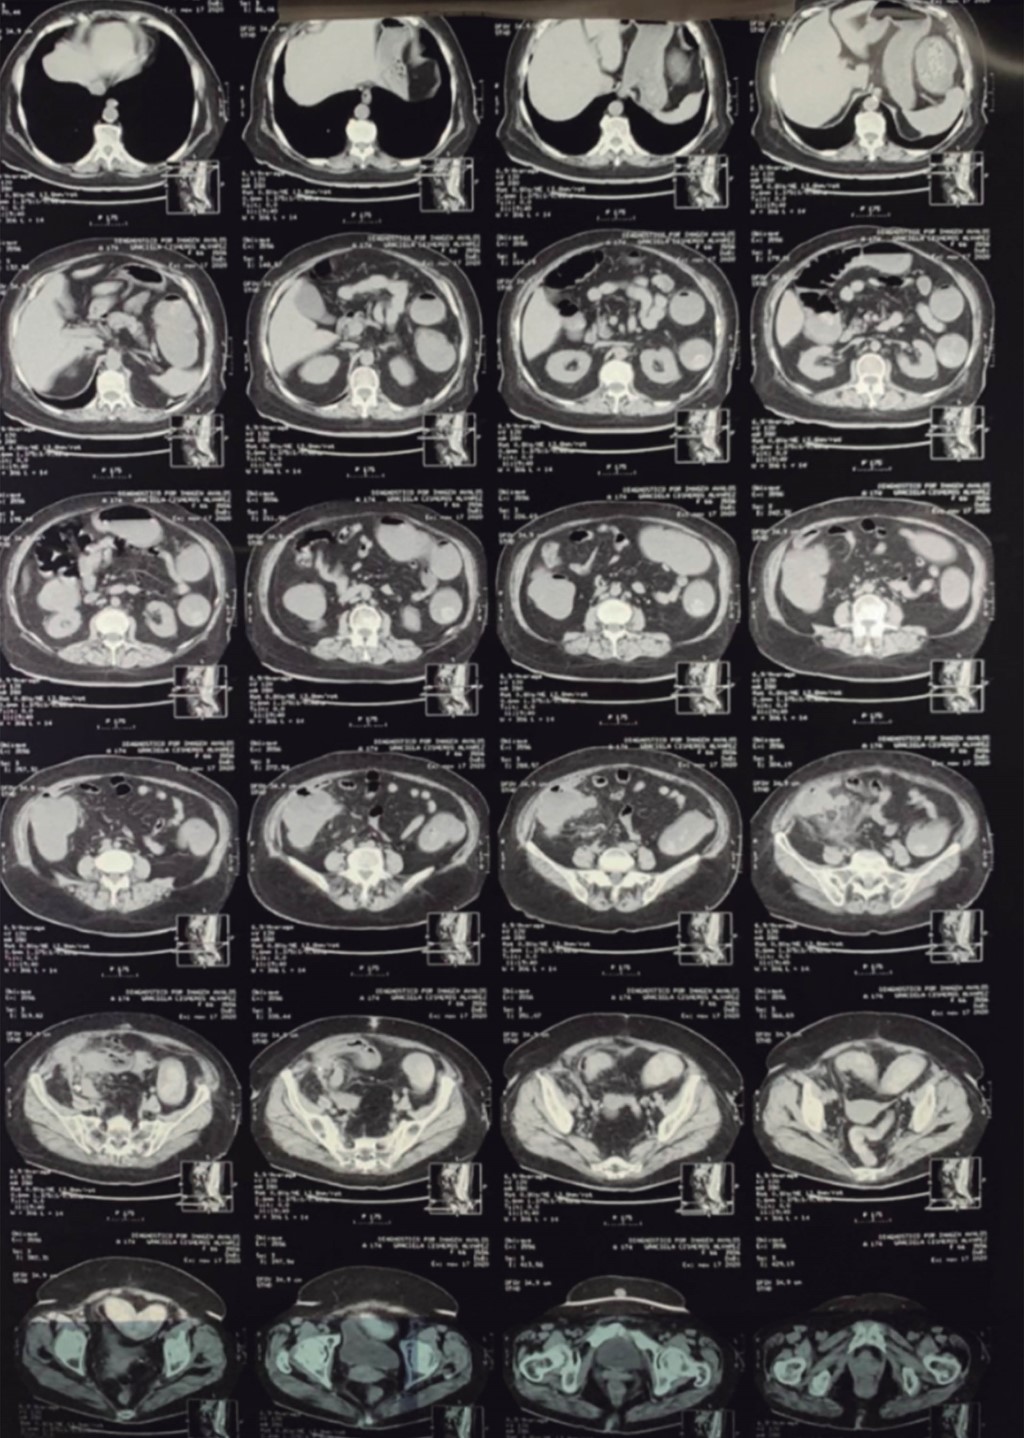

Paciente femenina de 66 años con antecedente personal de importancia de diabetes tipo 2, de 40 años de evolución, tratada con insulina, así como hipertensión arterial sistémica, de 25 años de evolución, tratada con IECA; antecedente quirúrgico de reparación de hernia umbilical hace 14 años, cesárea hace 34 años y fractura de clavícula hace dos años. Es admitida al servicio de urgencias por presentar dolor abdominal localizado en la fosa iliaca derecha, el dolor abdominal era crónico, con más de seis meses de evolución; lo había presentado pero había cedido. La semana anterior comenzó con dolor abdominal localizado en fosa iliaca derecha el cual cedía con medicamentos, asimismo síntomas de oclusión intestinal sin poder canalizar gases y no presentó vómito. A la exploración se encontró taquicardia, irritación peritoneal en fosa iliaca derecha, tumoración palpable en fosa iliaca derecha de alrededor de 7 × 10 cm y peristaltismo muy disminuido. Se le realizó una tomografía abdominal (Figuras 1 y 2) donde se observó una tumoración que se encontraba con probable perforación, lo mencionan como probable apendicitis complicada vs tumoración. Se decide realizar laparotomía exploradora encontrando líquido de reacción inflamatorio no purulento de aproximadamente 100 cc, se observa tumoración que depende del ciego tomando sigmoides, por lo que se decide practicar hemicolectomía derecha con ileostomía y cierre de cabo distal, así también se realiza resección del sigmoides de alrededor de 7 cm, realizando anastomosis de sigmoides término-terminal con técnica manual con sutura no reabsorbible. Se colocan drenajes cerrados hacia corredera derecha y drenaje cerrado a hueco pélvico. Se extraen piezas de patología y se envían. Se termina el procedimiento quirúrgico, pasa a recuperación y posteriormente a piso, se le indica ayuno por 24 horas y comenzamos con dieta enteral. La evolución es hacia la mejoría clínica, comienza gasto por estoma, siete días posterior a la cirugía se retiran los drenajes sin complicaciones, se refiere a servicio de Infectología quien da ciclo de antibiótico a base de tetraciclinas por seis semanas. El reporte de patología demuestra región de hemicolectomía (Figura 3) sin alteraciones del tejido linfoide en placas de Peyer, en la serosa se encuentran depositadas pseudomembranas de fibrina con neutrófilos. La válvula ileocecal y mucosa cecoascendente demuestran reacción inflamatoria mixta con numerosos piocitos que se extienden al tejido adiposo del mesoapéndice que alberga colonias bacterianas de Actinomyces spp. que conforman filamentos ramificantes y coronas radiales formando gránulos de azufre (Figura 4). El apéndice cecal demuestra periapendicitis aguda fibrinopurulenta y el tejido de sigmoides con pronunciado edema en sus paredes. Diagnóstico: Actinomyces invasor cecal, perforado con peritonitis aguda fibrinopurulenta secundaria. La paciente es vista en servicio de consulta externa de cirugía general con evolución favorable. Infectología recomienda esperar por lo menos seis meses libres de actividad inflamatoria y de tratamiento médico con antibiótico para planear la reconexión intestinal.

Figura 1

Figura 2